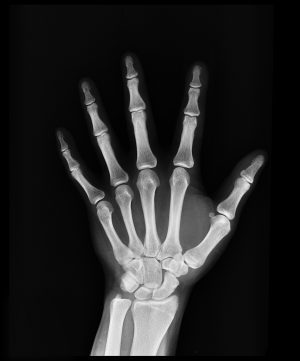

Images produced using x-ray machines are called radiographs. X-ray technicians use radiographs to look at the tissues and structures inside your body. When you have a broken bone, your doctor is able to look at the radiograph and see exactly where break is and how bad it is. This information is helpful in deciding how to best treat the injury.